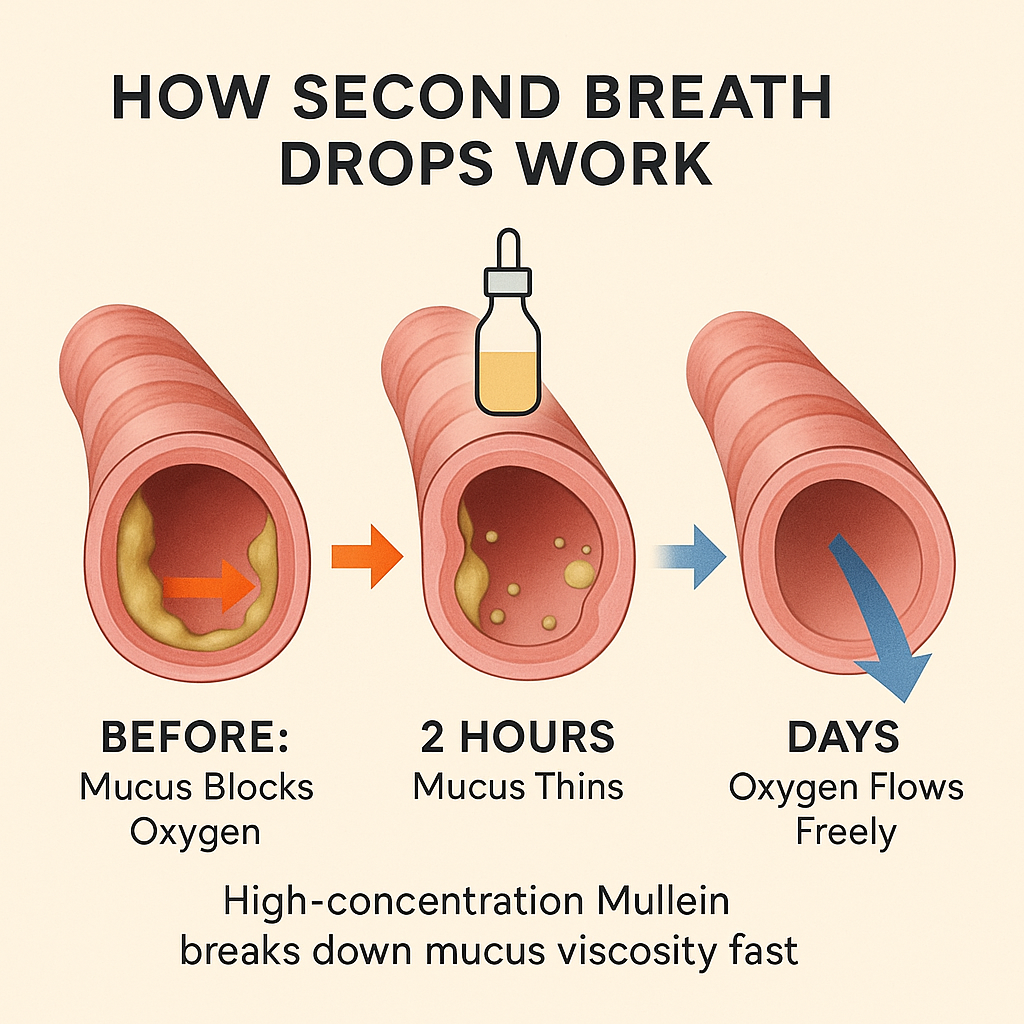

Breaks the panic cycle, restores natural breathing, and helps repair your lungs — giving you back your second chance at life.

From 'Fighting for Breath' to Breathing Clearly— What Your Inhaler Can't Fix

From 'Fighting for Breath' to Breathing Clearly— What Your Inhaler Can't Fix